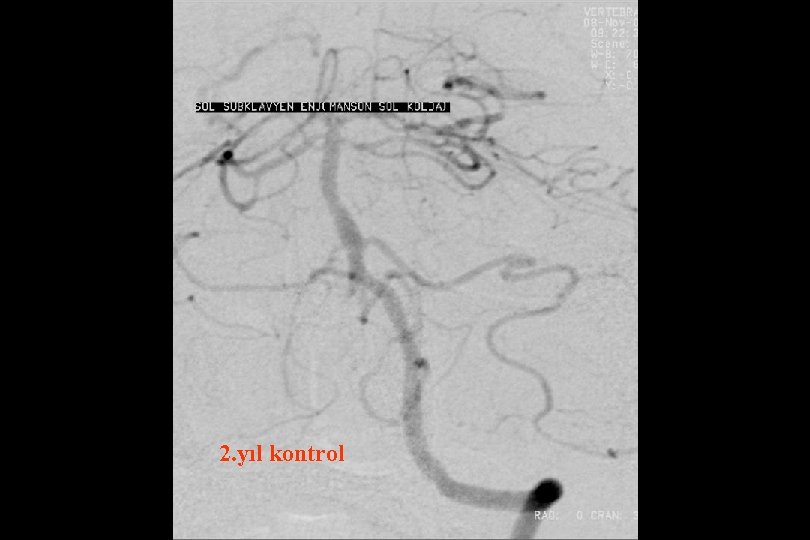

6 ay kontrol

52 y kadın efektiv/test edilmiş ikili antiagregan ted altında iken multipl TIA Basit PTA sonrası

1. Yıl kontrol

1 yıl kontrol PTA Sonrası